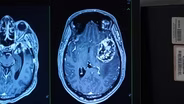

Brain cancers are complex, aggressive and there are few treatment options. A doctor at UNC Medical Center is using genomic sequencing to identify genetic mutations that might be driving a patient’s tumor. By knowing the mutation, the doctor can create a treatment plan that targets the mutation.